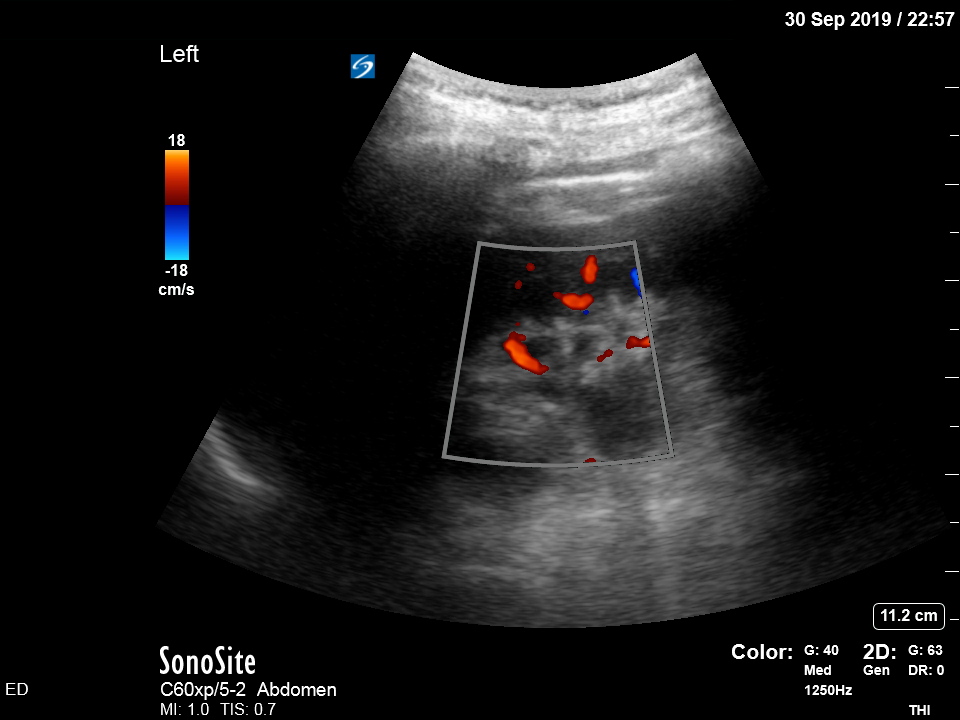

Bedside ultrasound was undertaken to assess for signs of ureteric obstruction.

There is moderate-to-severe hydronephrosis of the right kidney. There is mild hydronephrosis on the left. Colour flow doppler is used to demonstrate that the dilated pelvis and calyces are not normal blood vessels or aneurysms.

Hydronephrosis is dilation of the renal collecting system caused by increased pressure in the ureter, strongly suggesting downstream obstruction. Possible explanations for bilateral hydronephrosis include bladder outlet obstruction and bilateral ureteric obstruction. The former is unlikely in a freely urinating patient, especially female.

The history and findings suggest that the patient has developed bilateral ureteric obstruction from progression of retroperitoneal disease.